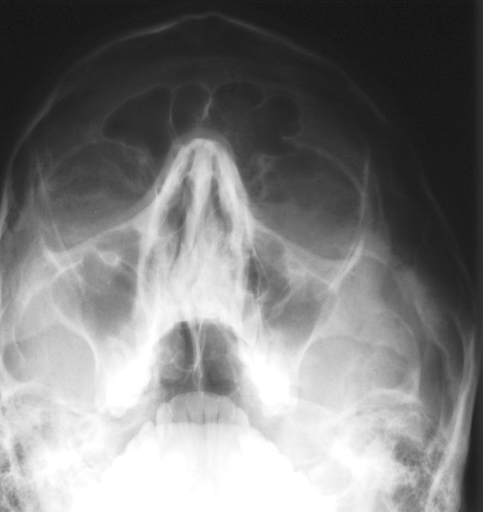

In this section, we report two series of experiments. The first one verifies the correctness or reliability of the micro-DE algorithm to find optimal projections compared to an exhaustive search when we are looking for 4 optimal projection angles out of 16 equidistant angles. In the second experiments, we still provide the results for exhaustive 4/16 selection but examine the evolutionary approach to get 4/180 and 8/180 to investigate the reconstruction accuracy of the micro-DE via correlation of the input image and the reconstructed image using 4/16 (exhaustive), 4/180 (micro-DE) and 8/180 (micro-DE). To conduct the experiments we used 50 images from IRMA dataset [34, 35], a benchmarking collection of 14,400 x-rays images. We selected 10 random classes out of 58 classes, and for each class, we randomly drew 5 images to be used in our experiments. Figure 4 shows the images we have used.

![]() |

[22∘, 67∘, 112∘, 157∘] with |

| [22∘, 56∘, 135∘, 169∘] with | |